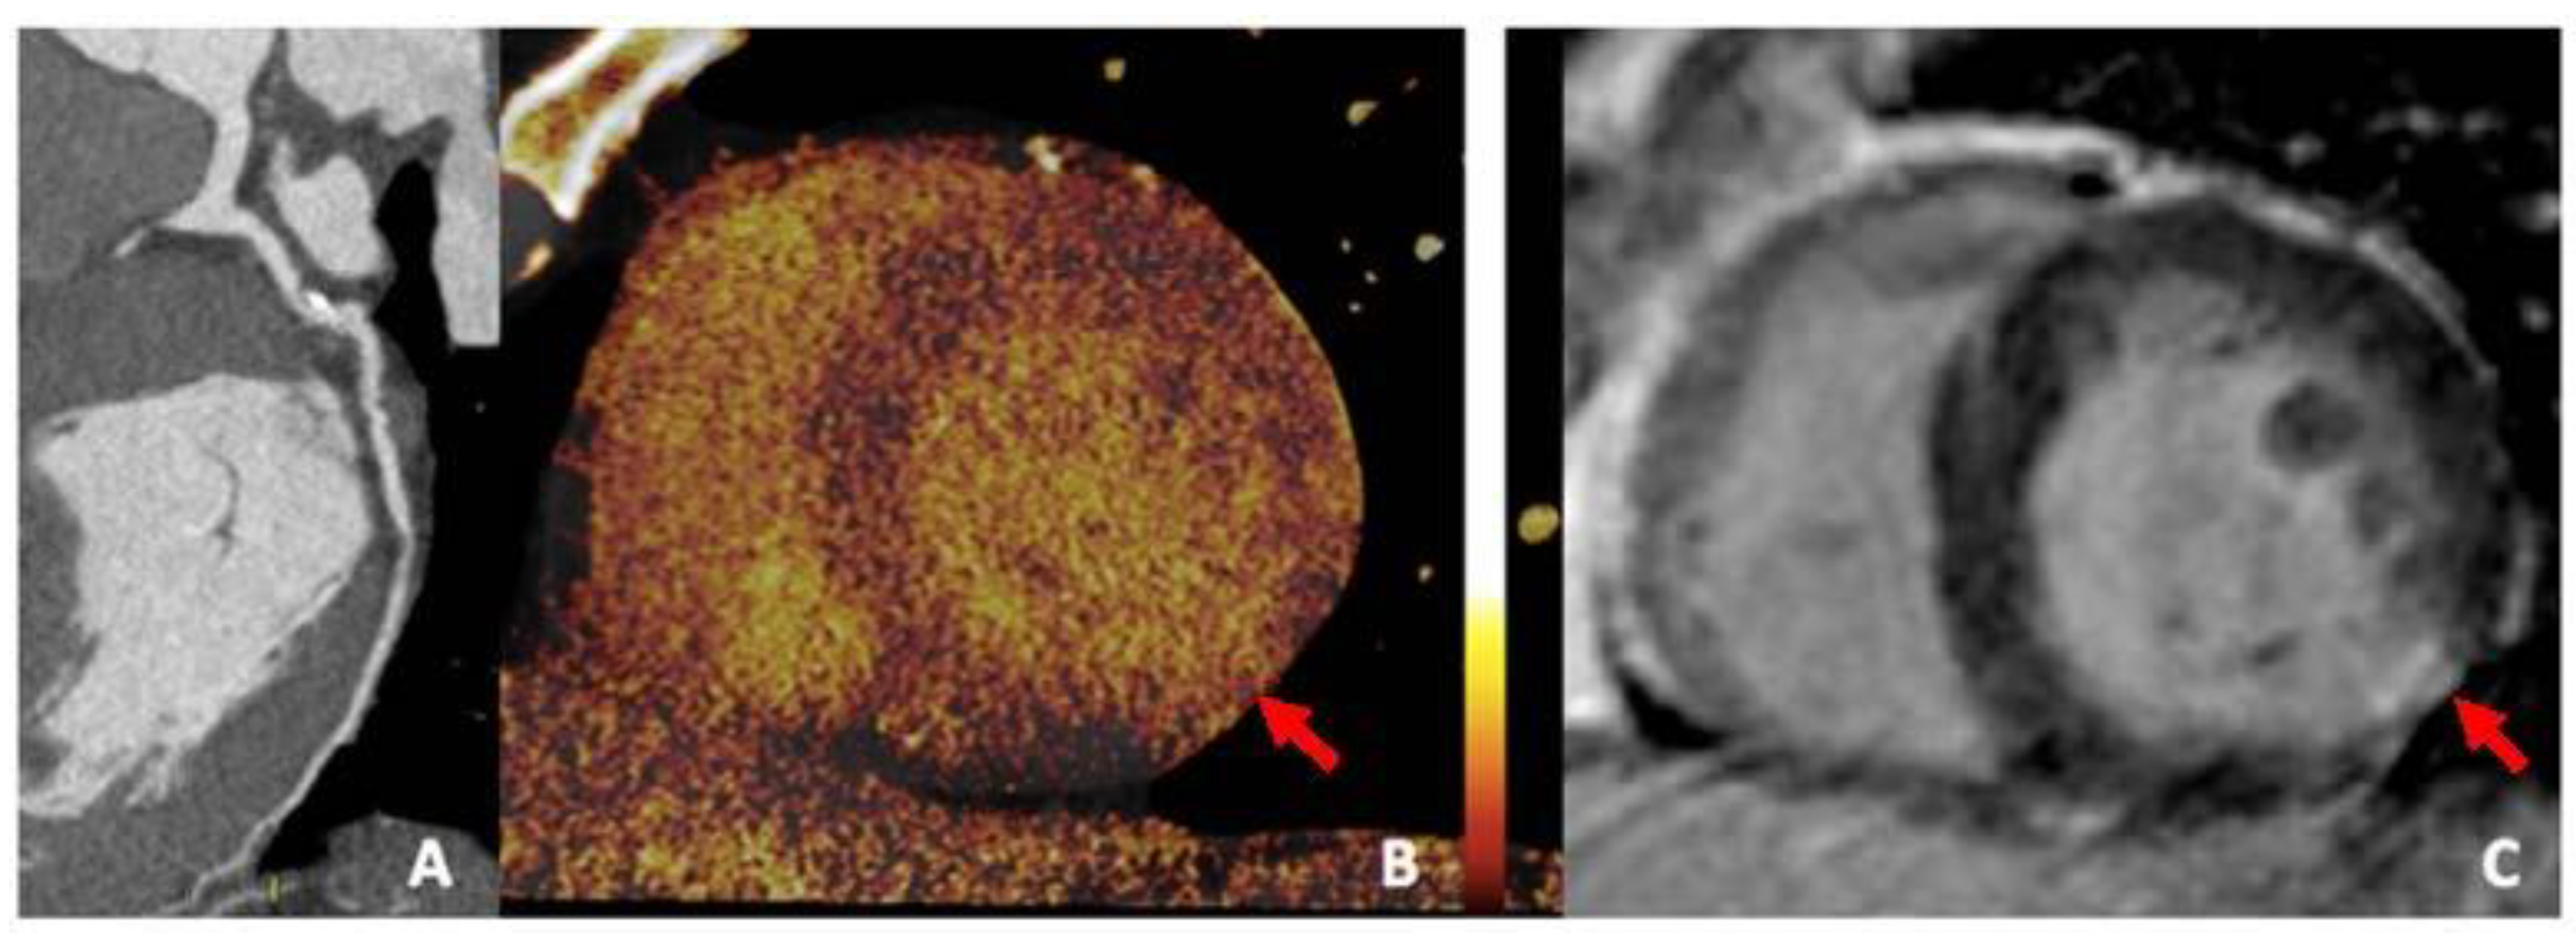

3.4. Iodine Perfusion Maps

- Nakahara, T.; Toyama, T.; Jinzaki, M.; Seki, R.; Saito, Y.; Higuchi, T.; Yamada, M.; Arai, M.; Tsushima, Y.; Kuribayashi, S.; et al. Quantitative Analysis of Iodine Image of Dual-energy Computed Tomography at Rest. J. Thorac. Imaging 2018, 33, 97–104. [Google Scholar] [CrossRef] [PubMed]

- Jin, K.N.; De Cecco, C.N.; Caruso, D.; Tesche, C.; Spandorfer, A.; Varga-Szemes, A.; Schoepf, U.J. Myocardial perfusion imaging with dual energy CT. Eur. J. Radiol. 2016, 85, 1914–1921. [Google Scholar]

- Delgado Sánchez-Gracián, C.; Oca Pernas, R.; Trinidad López, C.; Santos Armentia, E.; Vaamonde Liste, A.; Vázquez Caamaño, M.; Tardáguila de la Fuente, G. Quantitative myocardial perfusion with stress dual-energy CT: Iodine concentration differences between normal and ischemic or necrotic myocardium. Initial experience. Eur. Radiol. 2016, 26, 3199–3207. [Google Scholar]